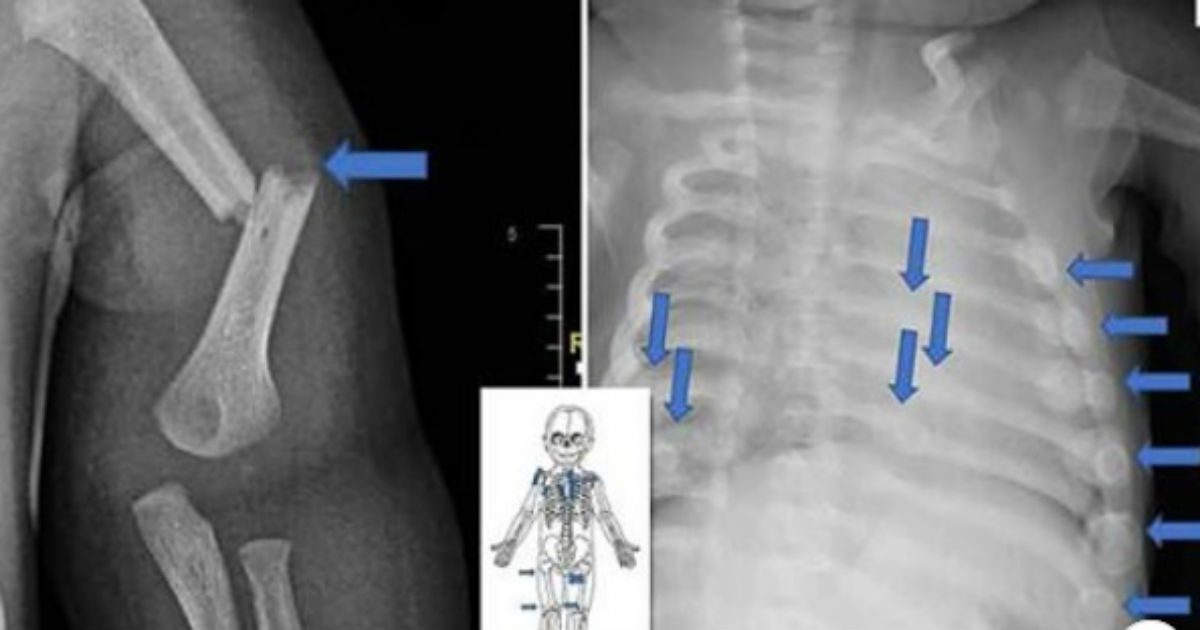

Porém, os médicos examinaram o pequeno e constataram que ele tinha mais de 20 fraturas nas costelas, nos dois joelhos e nos tornozelos. “Eles também perceberam que as fraturas foram causadas por força significativa de alguém”, disse o promotor Ryan Richter durante o julgamento.

Reprodução Polícia de Sussex – Algumas das fraturas que os pais causaram no bebê de quatro meses